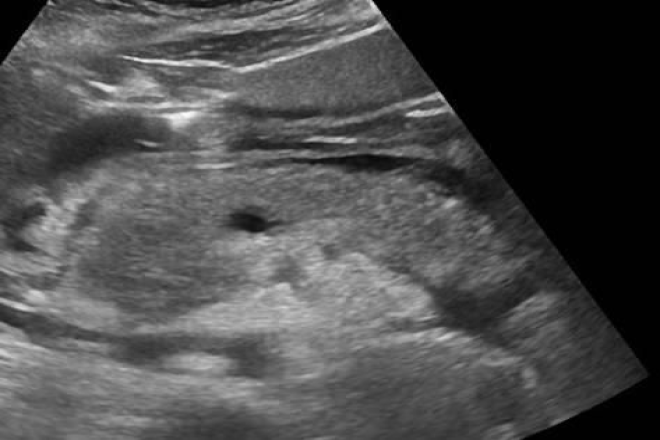

Técnica de exploración por ultrasonido del Bazo El páncreas es un órgano peritoneal mixto, con funciones exocrinas (secreción de enzimas digestivas al intestino delgado) y endocrinas (producción de hormonas como insulina, glucagón, polipéptido pancreático y somatostatina, que se liberan en la sangre). El páncreas tiene forma cónica con un proceso